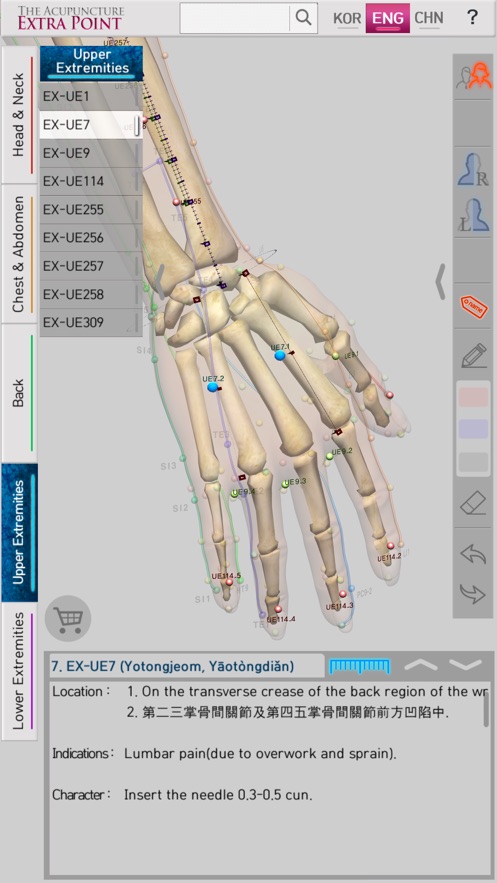

‘The Acupuncture of Extra Point’ was created by integrating Extra Point from the past, and the newly discovered New Point together as one product. It allows for easy comparison because it expresses 14 Main Acupuncture Point Meridian and the Extra Acupuncture Point together in a male and female 3D model. Easily zoom in and out with multi-touch so you can see the exact location of The Acupuncture Point. It is recommended for people who want to see both 14 Main Acupuncture Point Meridian and the Extra Acupuncture Point at the same time. Contents include accurate location, based book, function and character (how to use). Released in Korean, Chinese and English, which allows it to be used across the world! With realistic skin, bone, and internal organs in 3D human body model, everything is distinguished by rich colors so it is very easy to see. It is based on The International Standard Acupuncture Points of WHO, WHO`s International Standard Terminologies on Traditional Medicine in The Western Pacific Region, The acupuncture textbooks of the university of Asian Medicine and 'Huangdi Neijing - Lingshu’. It is supervised by professors and Korean medical doctors from Korea Medical University. * 14 Main Acupuncture Point Meridian - 12 Main Acupuncture Point, Governor Vessel (GV) Acupuncture Point, Conception Vessel(CV) Acupuncture Point.- See The Meridian 2.0

‘The Acupuncture of Extra Point’ is the only product in the world that expresses the Extra Acupuncture Point on male and female 3D human models.

‘The Acupuncture of Extra Point’ is easy to use because it displays The Extra Acupuncture Point on 3D human body model. As well, the Extra Acupuncture Point and 14 Main Acupuncture Point Meridians are displayed together with the accuracy, so you can easily compare.

In 'The Acupuncture of Extra Point’, the skin, bones, and internal organs of the 3D human model look realistic. The 14 Main Acupuncture Point Meridians and the Extra Acupuncture Point are distinguished by rich colors so they are very easy to see.